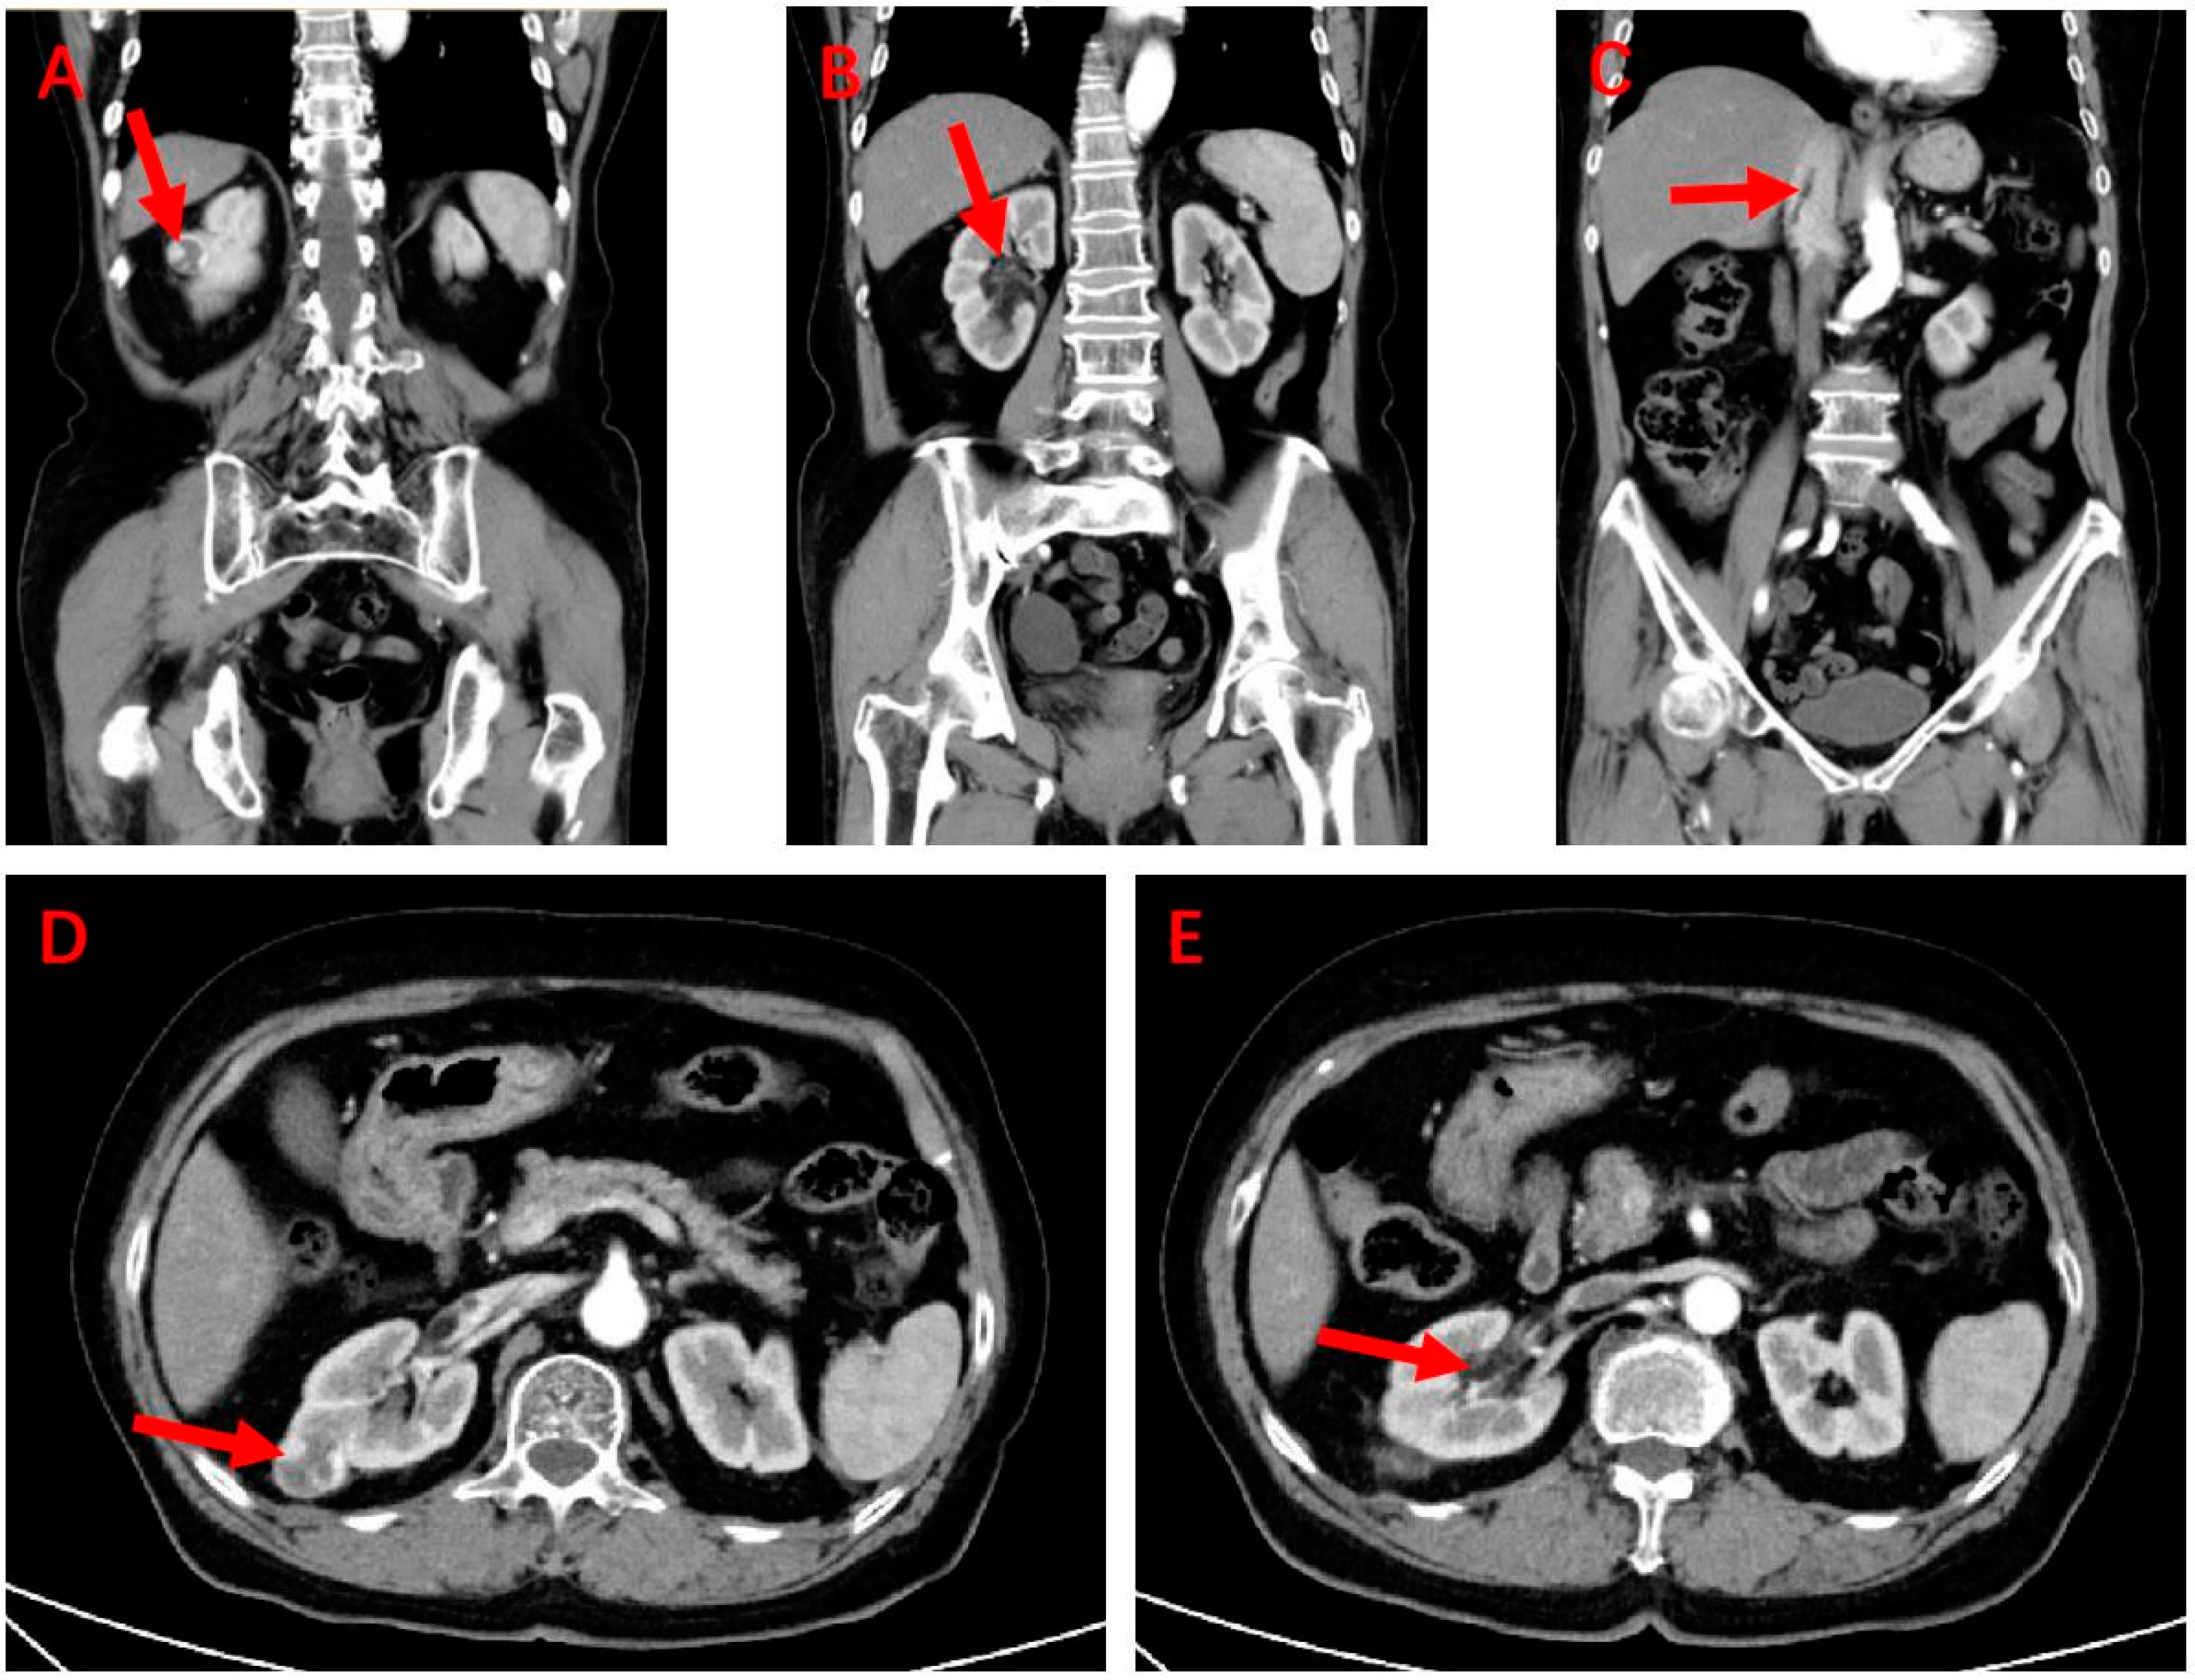

2.3. Imaging Examination